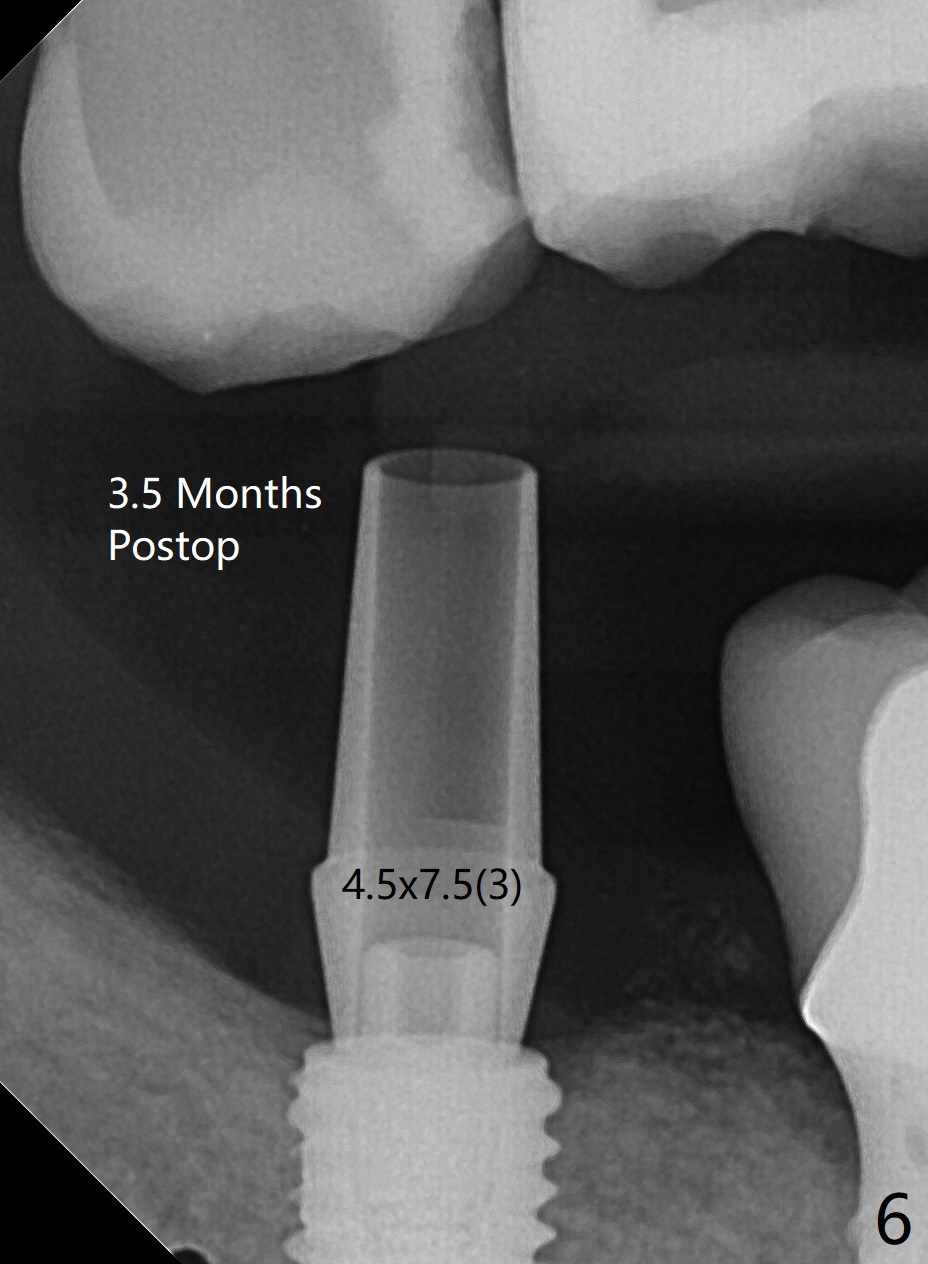

61岁女右下7导板钻洞,第一个钻头(环形钻)就有困难入位,部分磨去对合7近中腭侧牙尖(图一:*),钻头入位就好多了(图二:^,对比)。钻洞时发现骨质密度中等,所以最后钻头直径4.5毫米。不过无法用手植牙工具旋入植体,使用5.0毫米功螺纹钻头后,手工具就好用了,植体植入一定深度,扳手有空间插入,最后扭力30Ncm。第二个问题,当按照设计深度植入植体,用探针检查颊侧好像没有骨壁;加深大约0.5毫米(仿佛没有取到目的,颊侧骨板不明显)后,使用6毫米profile钻头,插入5.5x3毫米愈合基台(图二,三),在基台和颊侧牙龈之间植入异体骨粉,但愿帮助颊侧骨板再生。术后一周内敷料脱落,颊侧伤口愈合,好像骨粉没有流失。术后2.5月愈合基台脱落,换至小号基台(4向毫米),仍旧疼痛,休息2分钟,手拧紧,拍摄根尖片,仿佛就位(图四)。准备一周后调换稍微大,例如,4.8毫米基台。术后3.5个月,5.2毫米基台好像没有就位(图五:<),可能与远中牙槽嵴接触(*)。小一号基台仿佛就位(图六),与远中牙槽嵴无接触。术后4个月粘固后基台螺丝拧紧30Ncm。术后8个月,也就是粘固后4个月,牙槽嵴似乎试图覆盖植体平台(图七:箭头)。